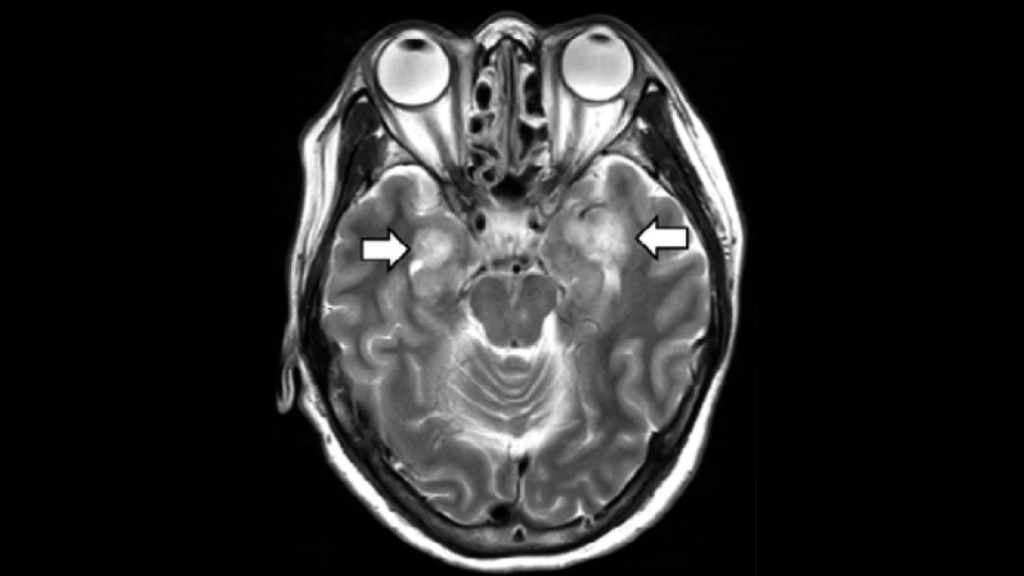

– Veç simptomave të njohura – temperatura, kolla dhe vështirësitë në frymëmarrje, disa pacientë zhvillojnë disfunksion të kapacitetit mendor, konfuzion, letargji, epilepsi, madje edhe sulm në tru – ka thënë Tsiodras në paraqitjen e vet të parë para opinionit grek.

Siç e ka shpjeguar ai, duket që virusi sulmon trurin dhe sistemin nervor madje te 15 për qind e pacientëve të sëmurë rëndë.

Është e njohur që virusi mund të përfshijë trurin dhe të shkaktojë përflakjen e tij, ndërsa problemet me thithjen e oksigjenit për shkak të frymëmarrjes së keqe mund të ndikojë në punën e trurit.